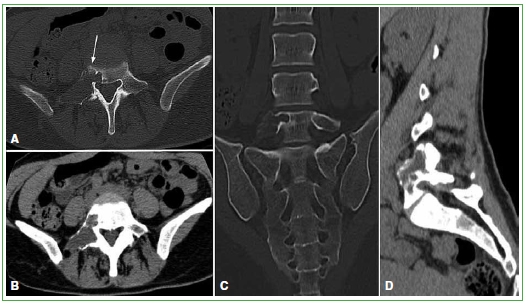

La anamnesis y el examen físico a cargo del Servicio de Ortopedia y Traumatología no revelaron otros hallazgos. Se solicitó una TC de columna lumbosacra que mostró una formación de aspecto lítico de bordes escleróticos y delgados tabiques internos completos, expansiva y centrada en el pedículo derecho de la quinta vértebra lumbar y con extensión al cuerpo vertebral, faceta y apófisis transversa derecha. Insuflaba y adelgazaba la cortical sin componentes extraóseos y sin comprometer los forámenes de conjunción (Figura 1).

Figura 1.

Tomografía computarizada. A. Ventana ósea, corte axial. B. Partes blandas, corte axial. C. Ventana ósea, corte coronal. D. Partes blandas, corte sagital. Lesión de aspecto lítico de bordes escleróticos y delgados tabiques internos completos, expansiva que adelgaza la cortical, centrada en el pedículo derecho de L5 y con extensión al cuerpo vertebral, faceta y apófisis transversa derecha. Presenta una pequeña área en “vidrio esmerilado” (flecha).